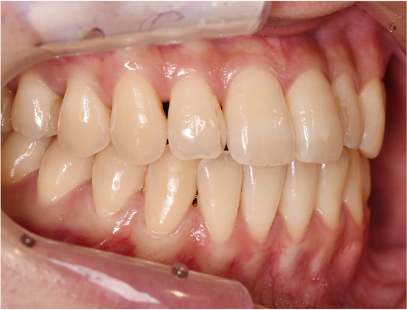

症例01|中学生の男子

前歯部の反対咬合

前歯部の反対咬合と上顎前歯のデコボコを主訴として来院されました。精査、診断の結果「前歯部に叢生を伴う反対咬合」と診断されました。

治療計画

非抜歯にて前歯の再配列、反対咬合の改善を行う事にしました。

治療前の写真と比べると前歯部の反対咬合は改善されて、上顎の前歯部のデコボコも綺麗に並べる事ができました。

また口元は上の歯が前に出たために口唇がへこんでいたことも改善されて男らしい綺麗な口元に改善できました。 治療期間は2年と6か月を必要としました。